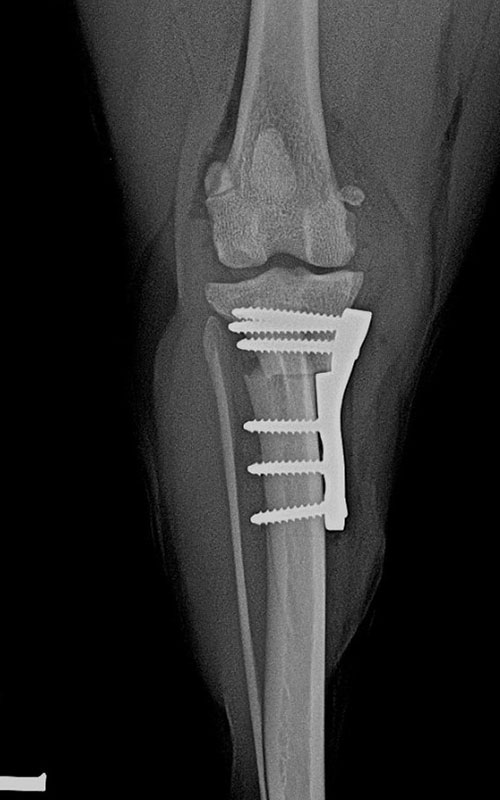

TPLO-M 2.4 with Smartvet polyaxial symmetrical TPLO plate (R15)

2.4 polyaxial butress symmetrical TPLO plate:

can be used with locking, polyaxial 2.4 torx head screws, the shift is 2.5mm. (for 5-12 kg dogs). In both cases, the insertion direction of the screws can be changed (polyaxiality !!!) to avoid the scew insertion into the joint.

Symmetrical design does not require right-to-left plates in stock, is made of steel (not titanium).

The insertion errors shown in the images were due to our routine.

The modification of TPLO is intended for the simultaneous correction of MPL and RACL. The new plate provides a high degree of stability and the polyaxiality gives the surgeon a high degree of freedom in choosing the direction of the screw insertion.